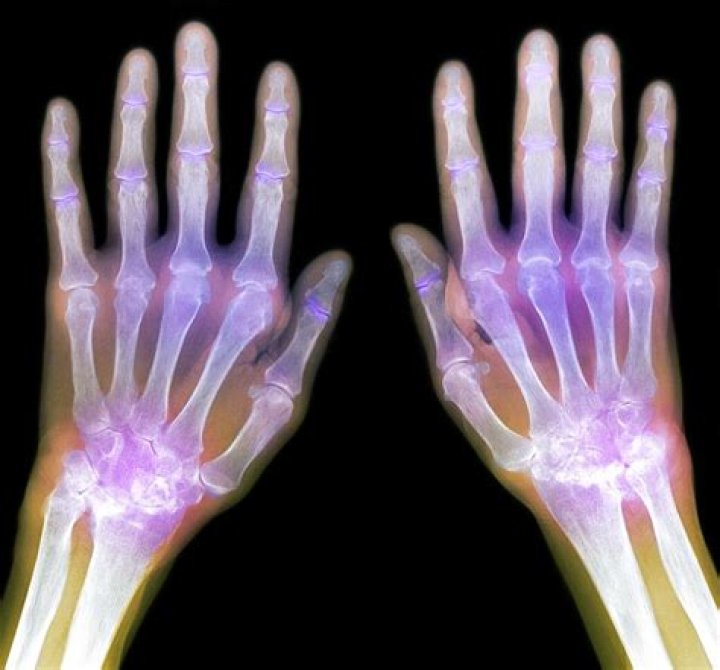

Score: 4.3/5 (28 votes) X-rays are often a good tool for determining if arthritis exists and, specifically, what type. Common types of arthritis include ...